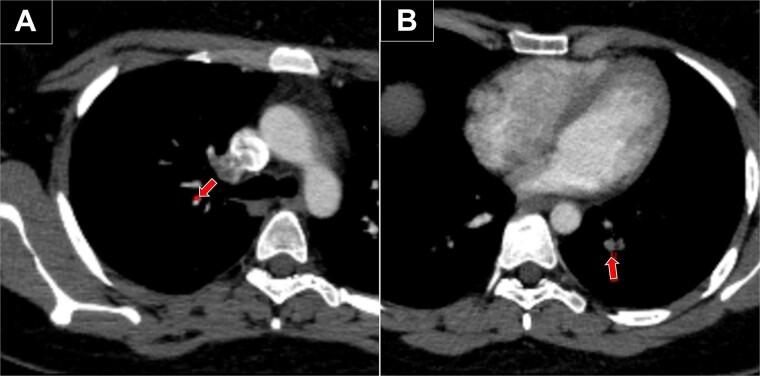

Venous thromboembolism (VTE) is a serious but rare complication of aesthetic surgery, with an incidence of 0.017% for liposuction and 0.01%-0.02% for augmentation mammoplasty. Despite the low incidence and appropriate patient selection, we present two cases of VTE in low-risk patients without hypercoagulability undergoing aesthetic procedures. In the first case, a 45-year-old woman with a history of anemia developed bilateral pulmonary embolism after ultrasound-assisted liposuction. In the second case, a 33-year-old woman with a history of oral contraceptive use developed deep vein thrombosis in the right upper extremity after augmentation mammoplasty. The patients were treated early and fully recovered after 12 months. This report highlights the importance of early diagnosis and treatment of VTE in aesthetic surgery, even in low-risk patients.

静脉血栓栓塞症(VTE)是美容手术中一种严重但罕见的并发症,抽脂术的发生率为0.017%,隆胸术的发生率为0.01% - 0.02%。尽管发生率较低且患者选择合适,但我们仍报告了两例在接受美容手术的无高凝状态的低风险患者中发生VTE的病例。第一例中,一名有贫血病史的45岁女性在超声辅助抽脂术后发生双侧肺栓塞。第二例中,一名有口服避孕药史的33岁女性在隆胸术后右上肢发生深静脉血栓形成。患者得到了早期治疗,并在12个月后完全康复。本报告强调了在美容手术中早期诊断和治疗VTE的重要性,即使是在低风险患者中。